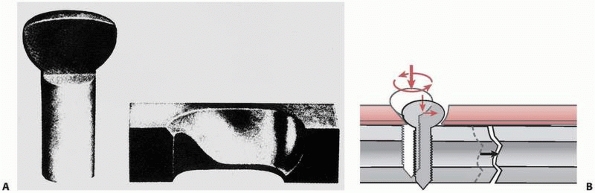

rotary load (torque) into compression between a plate and bone, or

between bone fragments. As shown in Figure 1-26,

the thread of a screw, if unwound from the shaft, is really a ramp or

inclined plane that pulls, for example, underlying bone toward

the fixation plate, causing compression between them.123 The basic components of a screw are shown in Figure 1-27.

Because of its function, the screw head and shaft should be free to

turn in the plate; otherwise the compressive force generated may be

limited. (This doesn’t apply to screws that are designed to be threaded

into the plate holes in locking plates.) One common problem is that

sometimes threads are tapped into both bone components. The bone

component in which the screw head will rest should be drilled oversize

to allow the shaft of the screw to turn freely. Tapping is necessary in

cortical bone so that the torque applied by the surgeon is converted

into compression instead of cutting threads and overcoming friction

between the screw thread and bone (Ft in Figure 1-26) that it is being driven into (Fig. 1-28).75

This mode of loading could occur during functional use; for example,

with a dynamic compression plate (DCP) but not a locking plate. The

screw should be tightened against the DCP plate to the maximum extent

possible and the tightening torque effectively transferred to

compressive force between plate and bone (see Fig. 1-28).

The screw holds the plate against bone partly by frictional contact,

which depends on the frictional force generated between the

undersurface of the plate and bone. The frictional force is directly

dependent on the compressive force generated by the screws. If any

sliding occurs between the plate and bone, bending load will be

transferred from the head of the screw into the plate, where

screw-plate contact occurs. Bending loads perpendicular to the axis of

the screw, along with possible stress corrosion and fretting corrosion,

may cause the screws to fail rapidly in fatigue. Zand et al168

showed that screws tightened against a plate with only 10% to 15% less

force than the maximum possible failed in less than 1000 loading

cycles, by bending fatigue, compared with fully tightened screws that

were able to sustain over 2.5 million loading cycles. Screws that lock

into the plate reduce this problem. Small fragment screws, around 4 mm

outside diameter, can fatigue because their core diameters are small.

The trade-off in use of these devices is choosing a screw with a larger

core diameter and shallower thread to reduce the possibility of

fatigue, or a smaller core diameter and deeper thread to increase

purchase strength in bone.111